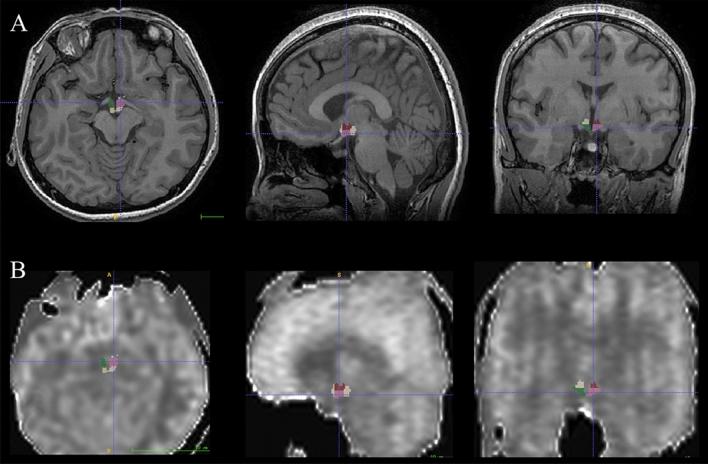

Hypothalamus is a crucial deep brain area that is responsible for the integration and coordination of various brain functions. The altered perfusion of hypothalamus during headache caused by medication-overuse headache (MOH) was previously unknown. In the current study, the altered perfusion of hypothalamic subregions in MOH patients was investigated using state-of-the-art 3D pseudo-continuous arterial spin labeling (PCASL) MR imaging. In this study, 29 normal controls subjects (NCs) and 29 MOH patients underwent 3D PCASL and brain structural MR imaging. The hypothalamus was automatically segmented into 10 subunits and the volume of each subunit was automatically determined using Freesurfer software (v7.4.1). All segmented hypothalamic subunits were converted to individual hypothalamic subunit masks. The cerebral blood flow (CBF) images were coregistered with the raw brain structural images and resliced. The CBF value of each hypothalamic subunit was extracted from the warped CBF images. The volume and CBF value of each hypothalamic subunit were analyzed using the independent sample T test and Mann-Whitney U test, receiver operating characteristic (ROC) curve analysis, and Pearson and Spearman correlation analysis. Hypothalamic subunits with significantly decreased perfusion were located in the left posterior, left tubular superior, right anterior-inferior, right tubular inferior, right tubular superior, right posterior subunit and the entire right hypothalamus [CBF value for MOH vs NC (mL/100 g·min): 48.41 ± 6.75 vs 54.08 ± 11.47, 44.44 ± 4.79 vs 48.11 ± 7.73, 41.49 (32.90, 61.46) vs 49.38 ± 10.47, 46.62 ± 7.04 vs 53.90 ± 11.75, 42.12 ± 5.74 vs 47.02 ± 9.99, 42.79 ± 5.15 vs 47.93 ± 10.48 and 43.58 ± 5.06 vs 48.65 ± 9.33, respectively] in MOH compared to NC (P < 0.05). ROC analysis for these positive subunits revealed that area under the curve was 0.658-0.693, and ROC curve for left posterior subunit had the highest specificity of 93.10% while the entire right hypothalamus had the highest sensitivity of 72.41%. Further correlation analysis showed that the CBF value of the left posterior, right anterior-inferior, right tubular superior, whole right hypothalamus presented significantly negative correlation with Hamilton Depression Scale (HAMD) score (P < 0.05). Hypoperfusion of hypothalamic subunits may contribute to the understanding of MOH pathogenesis, and the 3D PCASL could be considered as a potential diagnostic and assessment tool for MOH.